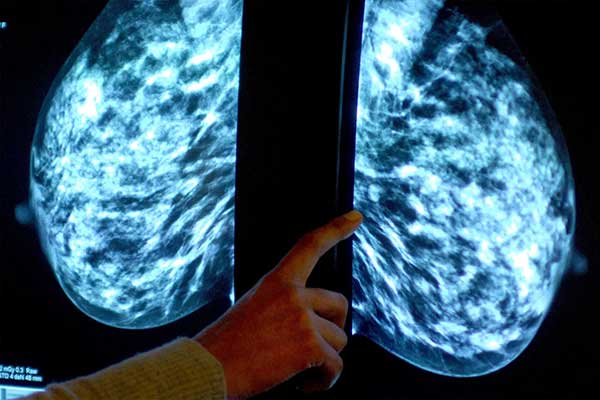

- Balasubramanian AA, Al-Heejawi SMA, Singh A, Breggia A, Ahmad B, Christman R, Ryan ST, Amal S. Ensemble Deep Learning-Based Image Classification for Breast Cancer Subtype and Invasiveness Diagnosis from Whole Slide Image Histopathology. Cancers. 2024; 16(12):2222. https://doi.org/10.3390/cancers16122222

New Research Shows AI Can Revolutionize Breast Cancer Diagnosis

BioE Assistant Research Professor Saeed Amal was featured in the Lagatar News article “New Research Shows AI Can Revolutionize Breast Cancer Diagnosis.”

New AI Architecture Can Detect Breast Cancer With a Near-Perfect Accuracy Rate

BioE Assistant Research Professor Saeed Amal and his research team have developed a new AI architecture that has detected breast cancer with a 99.7% accuracy rate. His research was published in the journal Cancers. He has submitted an invention disclosure with the Center for Research Innovation on the idea.